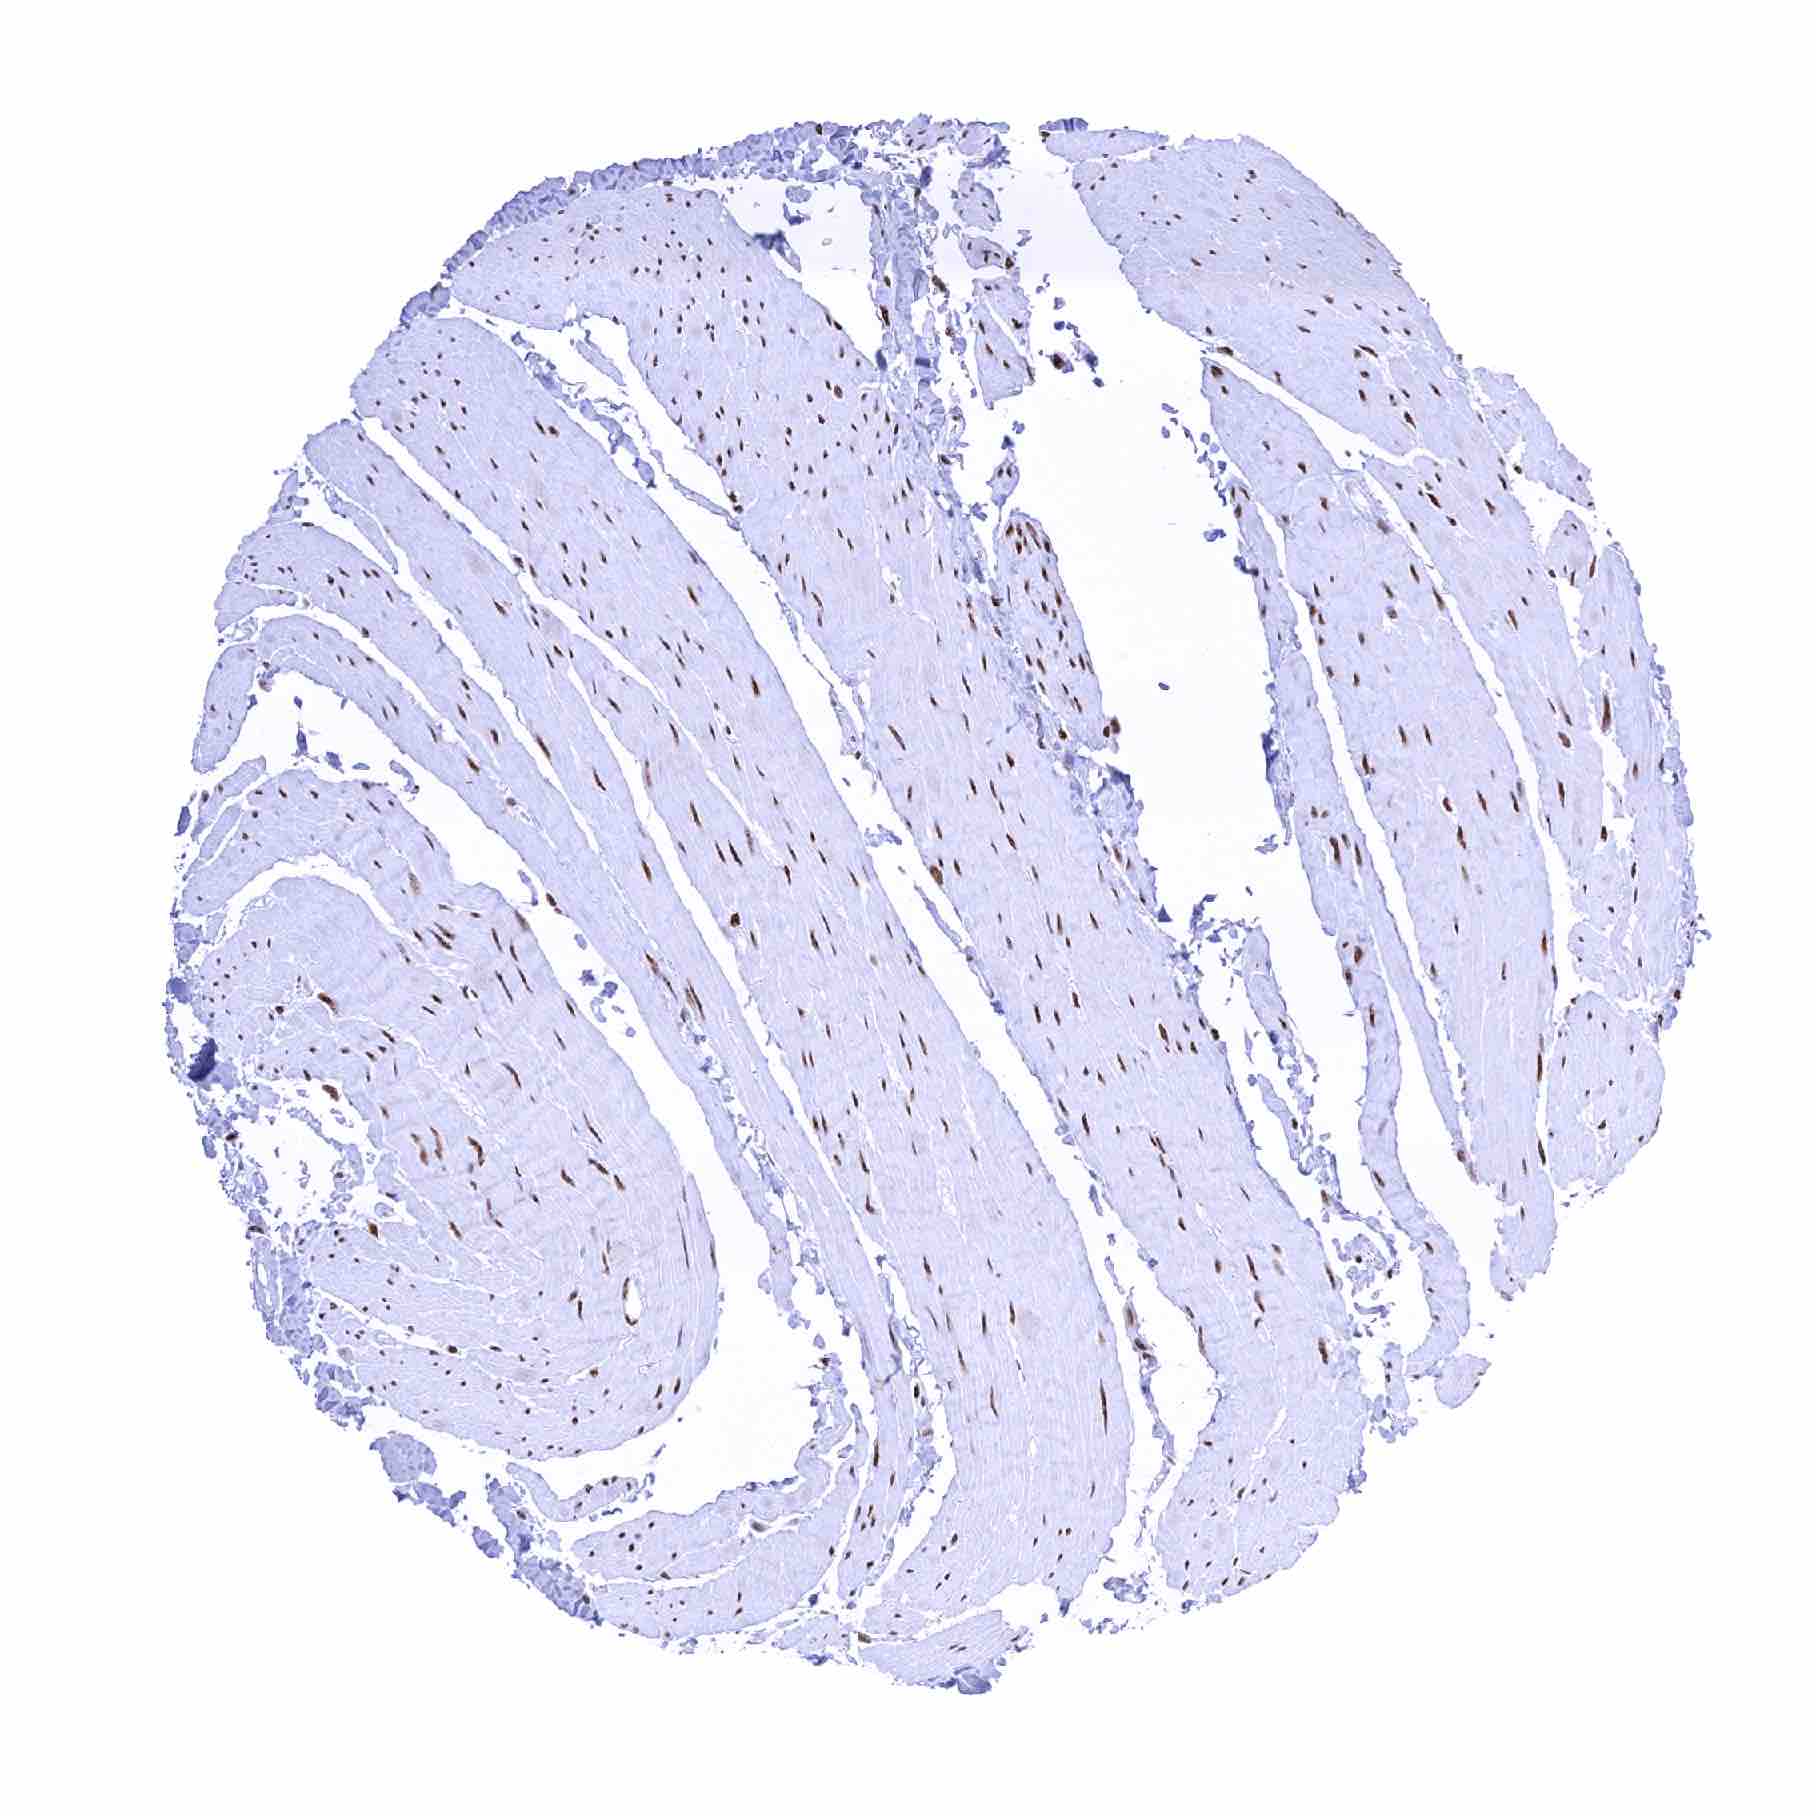

Normal Tissue Gallery- GTX640556

53BP1 antibody [HMV324] HistoMAXTM

Heart muscle